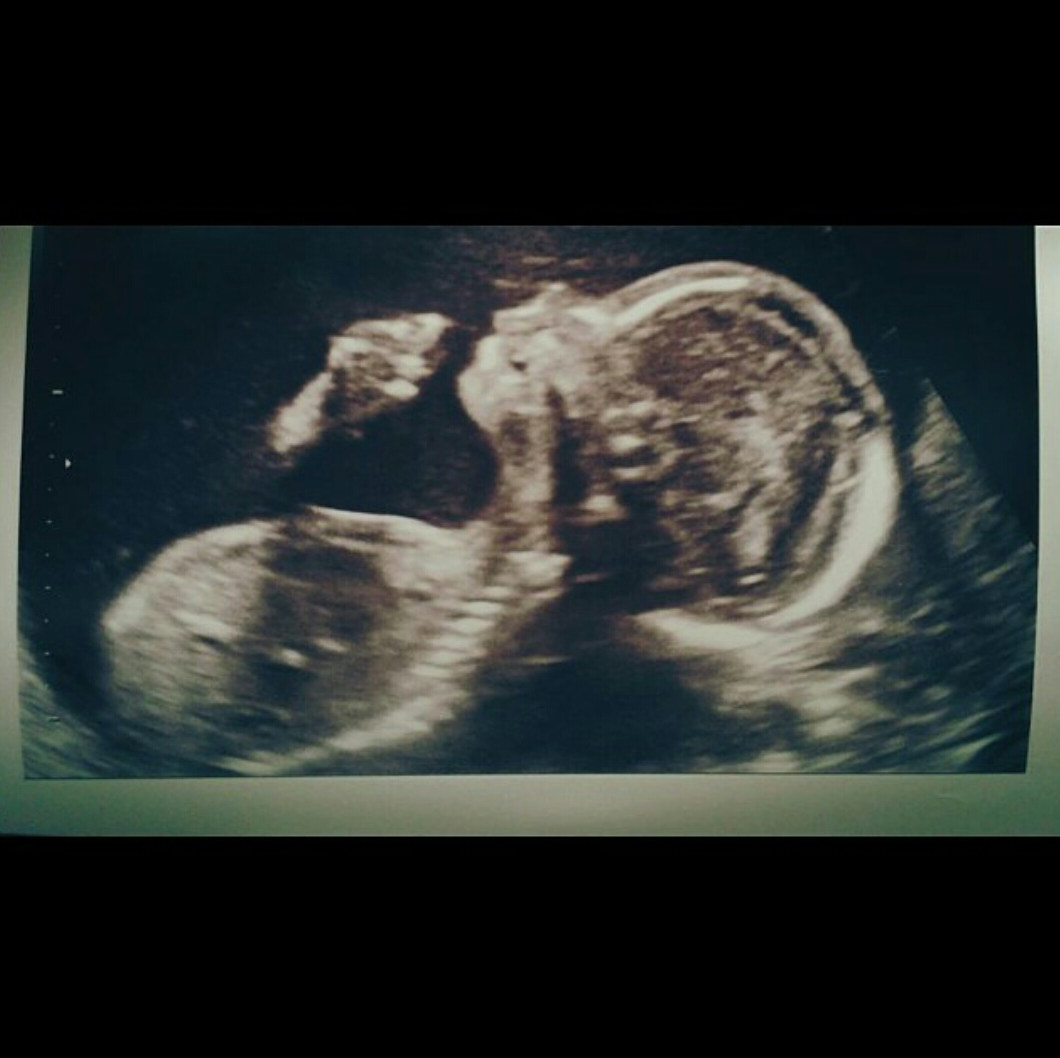

Snooki shared an ultrasound pic of her little girl. With the lines: “look she is already applying lipstick”